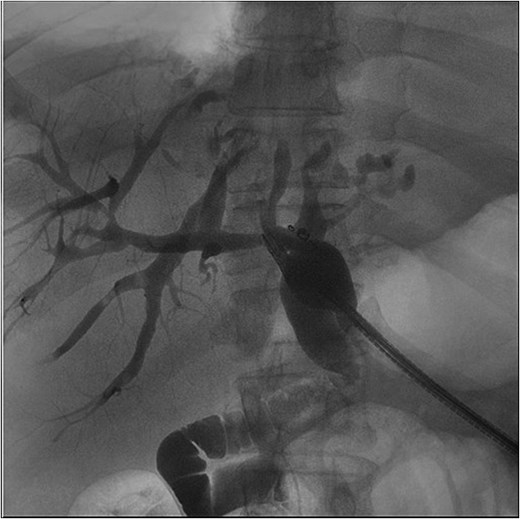

The patient presented the following day with fevers and new chest pain. He underwent a computed tomography angiography (CTA) chest and abdomen/pelvis, which revealed a left lower lobe consolidation and a moderate pericardial effusion. His hepatic abscess had increased in size to 7.2 × 5.5 cm (Fig. 2). Cardiology was consulted, and a bedside echo was performed, which found acute pericarditis. He was admitted and started on IV antibiotics and colchicine for his pericarditis. GI subsequently performed an ERCP, which showed no biliary or anastomotic stricture (Fig. 3). It was thought that it was likely a choledochal cyst, and the plan was for elective left hepatectomy. He was transitioned to oral antibiotics and discharged with colchicine for 3 months.

First readmission CT scans. (A) CTA chest images in the axial and sagittal planes illustrating the newly developed pericardial effusion. (B) CTA abdomen/pelvis images in the axial, coronal, and sagittal planes. These illustrate the abscess increasing in size.